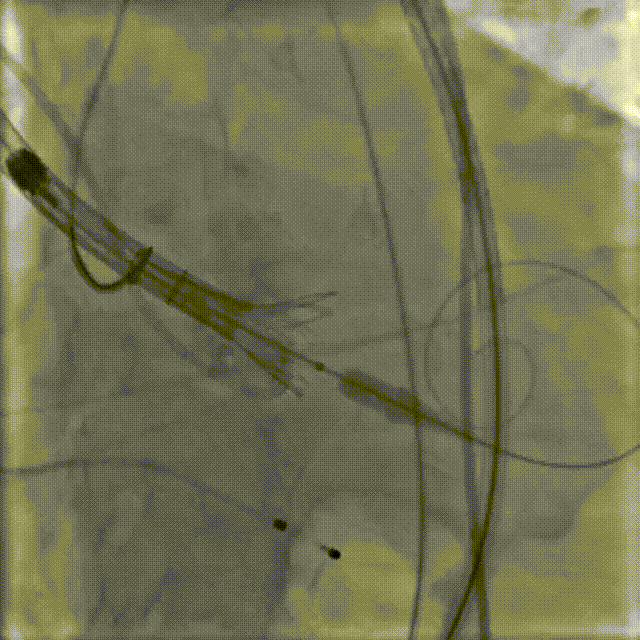

根据术前测量分析,采取右侧股动脉作为主入路,左股为辅入路。置入猪尾进行根部造影,造影可见主动脉根部钙化重,瓣叶活动度低。

1.冠脉造影评估

2.主动脉瓣根部造影

右窦居中,无窦最低

3.微创Alwide 20mm球囊充分预扩张

造影观察左右冠显影情况